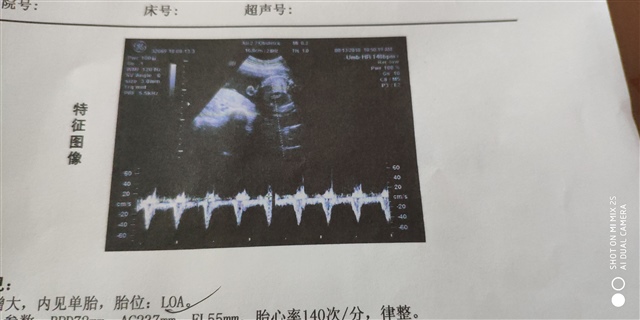

孕26周+1天

女